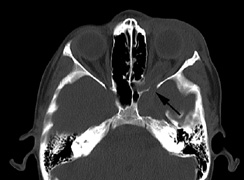

The PWS may not entirely respect the midline, possibly a reflection of transmedian innervation.212 The lesion grows proportionally with the child, often becoming darker in color. 213 The overlying skin may develop nodularity or hypertrophy in two-thirds of patients (by the fifth decade).214 Treatment with a pulsed-dye laser may significantly improve the appearance, but recurrence (i.e., redarkening) is possible.215,216 A deficit in the number of perivascular nerves in port-wine stains suggests that abnormal neural modulation of vascular flow may be involved in their pathogenesis.217 Intracranial leptomeningeal capillary vascular malformation (Figs. 21 and 22) is associated with seizures and contralateral neuromuscular weakness. Central nervous system involvement correlates highly with ipsilateral involvement of the V1 dermatome by a PWS.208,218

It has been hypothesized that the calcific changes reflect cellular anoxic injury secondary to venous stasis/poor drainage.219,220 Abnormal autonomic innervation has also been reported in association with the malformed cortical vessels—innervation only by noradrenergic fibers.221 Studies suggest that the normal increase in brain-blood flow to accommodate increased metabolic demand during seizure activity is blunted in affected brain regions of SWS.222 Thus, seizures in the setting of impaired perfusion may be exacerbating brain injury. Periods of contralateral weakness (days to weeks) can follow a prolonged seizure episode.206,223 When seizures begin early in life, the risk of developmental delay is much higher. In a review of 171 patients with a facial PWS and associated intracranial vascular malformation, 80% were found to have a seizure disorder. Of those, 75% with seizures had an onset during the first year of life, rising to 95% before age 5 years. Nearly all patients had a PWS that included (or was limited to) the V1 distribution. Developmental delay was strongly associated with seizures (71% of children with seizures as compared to 6% without seizures).224 Glaucoma affects 50% to 70% of SWS patients224,225 and it is a therapeutic challenge. From the time of diagnosis, the intraocular pressure, the optic discs, and the corneal diameters need to be measured intermittently, even if an occasional examination under anesthetic is required. The development of glaucoma appears to follow a bimodal age distribution: early-onset/congenital-type and later-onset. The glaucomatous eye is nearly always on the same side as the PWS.224 The highest risk for glaucoma appears to be when the PWS involves both the upper and lower lid: 72% vs. 21% for VI-only (upper eyelid) involvement in one study.224 The bimodal age distribution of glaucoma suggests that more than one mechanism is involved. Angle abnormalities (“trabeculodysgenesis” with or without flat anterior iris insertion) have been reported in association with the early-onset/congential type.225 Other proposed mechanisms include uveal capillary dilation226 and elevated episcleral venous pressure. Reports of blood in Schlemm's canal on gonioscopy support the idea of increased episcleral venous pressure pathomechanics.227,228 Glaucoma in SWS often responds poorly to medical therapy alone. The “trabeculodysgenesis” of early onset Sturge-Webber glaucoma is reported to be similar in gonioscopic appearance to primary congenital glaucoma.229 On this basis, goniotomy was suggested as a treatment of choice in early-onset SWS glaucoma. One group looked at the success of goniotomy, trabeculotomy, trabeculectomy, laser trabeculoplasty and medication in the management of SWS-associated glaucoma.230 In the early onset subgroup receiving goniotomy, median stable interval of intraocular pressure reduction after one procedure was 8 months; with multiple goniotomies and the addition of medical treatment, the median stable interval was extended to 9 years. Other investigators have found that goniotomy alone may be insufficient, requiring filtering surgery at some point. However, trabeculectomy carries a significant risk of choroidal expansion in association with hypotony. Theoretically, the risk may be higher when there is increased choroidal vascularity in association with the facial PWS—a “tomato ketchup” fundus.231 Often, there is associated increased tortuosity of the retinal vessels as well. Placement of a prophylactic posterior sclerotomy prior to filtering surgery to prevent choroidal expansion is controversial.232 Cryo- or thermocoagulation of the ciliary body in combination with medical therapy may be an alternative to surgery.233 KLIPPEL TRENAUNAY—WEBER SYNDROME Klippel-Trenaunay syndrome consists of combined capillary, lymphatic, and venous malformations, in association with varicosities and limb enlargement (Fig. 23). In the majority of cases, the lower limb is affected.234,235